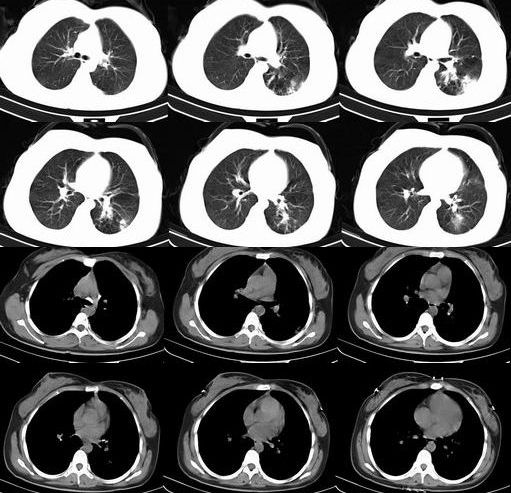

球形肺炎是大叶性肺炎的一种特殊表现[1],以肺的渗出实变为主。它的机理未明,可能是由于抗生素的广泛应用,大叶性或节段性肺炎发展受到限制而形成球形,其形成又与病缘菌的毒性数量及机体的免疫能力有关。病人多有感然症状,某些病人无明显感然症状。病变呈球形或椭圆形,大小不等,病灶密度多均匀,ct值稍低于软组织密度;或中央密度高,边缘密度低,显示晕圈状改变;有时可见空洞[2]。病灶边缘比较规则,也可不规则,有毛刺或呈锯齿状改变,但较模糊。位于肺周区,贴近胸膜,部分病栽表现为两侧缘垂直于胸膜,呈刀切样平直边缘。病灶周围血管纹理增多、增粗、常有局限性胸膜增厚。球形肺炎抗炎两周后,病灶即有缩小,最后能完全吸收。

球形肺炎:病变密度相对较淡,中央密度略高,ct图片上密度较为均匀,增强中央可出现无强化区。病变邻近胸膜反应较为显著,可表现为增厚、粘连(可以比较广泛),病变内可以见到大血管的贯穿,周围及近肺门侧可以见到血管纹理增多、增粗,可有支气管充气征象,两侧可垂直于胸膜或呈方形,边缘可为刀切征,它可以出现毛刺样的类似改变,短期内抗炎治疗有效。